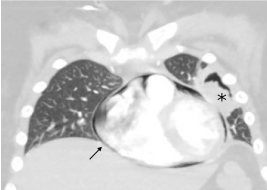

On PICU day 19, our patient acutely developed hypoxemia and hemoptysis requiring intubation with positive pressure ventilation (PPV). Although her post-intubation radiograph did not reveal PTX, CT chest performed within 2 hours demonstrated a new left sided PTX (Figure 3) requiring thoracostomy tube placement. A percutaneous CT guided biopsy was performed with initial microscopy demonstrating filamentous fungi suspicious for Aspergillus spp. Due to severity of her ARF and need for PPV she had persistent PTX, air-leak, and progressive PPC. On day 24, she developed PH leading to hemorrhagic shock and cardiopulmonary arrest with inability to recover spontaneous circulation.

Figure 3. Chest CT demonstrating pneumothorax (white asterisk) with adjacent aspergilloma (black asterisk) and expanding pneumopericardium